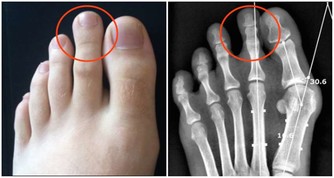

特別藥物:須飲水2000毫升以上為削弱特別藥物毒性,避免對器官特殊是對腎贓的損傷,請求服用藥物後每日必需飲水2000毫升以上。比如:在服用抗痛風藥後,應大批飲水,以下降黃嘌呤結石以及腎內尿酸沉積的風險;服用排尿結石的藥後,也需大批飲水,以沖刷尿道、稀釋尿液,從而下降尿液中鹽類的濃度和尿鹽沉澱的機遇。